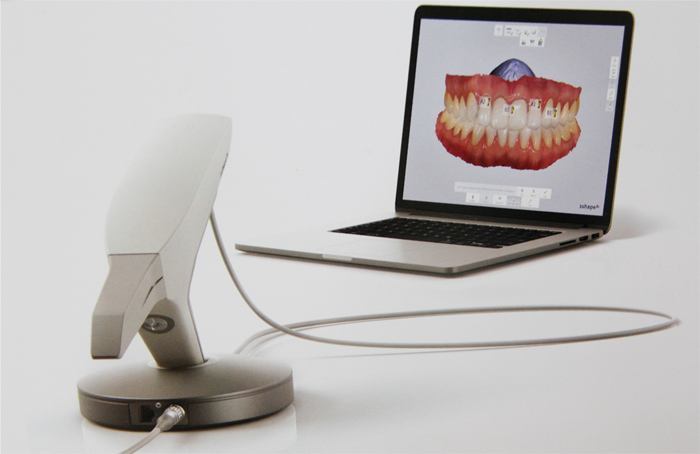

海涛“一天得”全口种植牙技术是海涛口腔的特色技术,该技术对口腔机构数字化水平要求非常高,医生经过CBCT扫描和3-SHAPE口内扫描,就可以准确获取缺牙者牙槽骨精密数据,然后定制数字化导板,这就好比生活中用的定位导航一样,确保手术过程中将种植体植入术前所精心设计的准确位置,以此来保障患者戴冠后能得到媲美真牙的咀嚼能力。